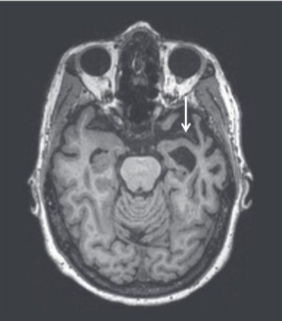

Frontotemporal dementia (Picks disease)

Frontotemporal dementia

Most common form of dementia in patients under 65

20% have known familial cause

40% have strong family history

Poor outlook - limited treatment and slow progression

Often restricted to one hemisphere

Lots of variance in presentation